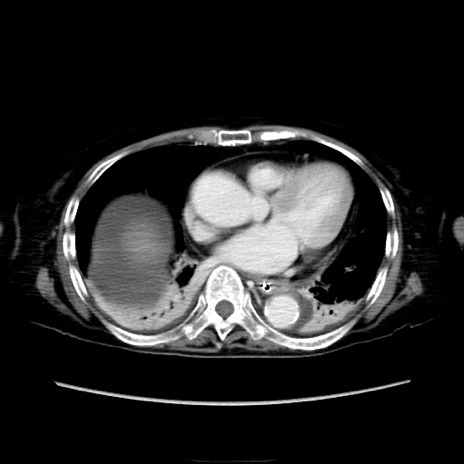

症例40(横断像)

【症例】90歳代女性

【主訴】腹痛・嘔吐

【現病歴】 食欲低下、嘔吐があり昨日他院受診。肺炎と診断され入院となる。入院後より腹部全体に圧痛あり。胃管留置され経過みていたが、症状持続するため、

当院転院となる。

【既往歴】胸椎圧迫骨折、胆石症

【身体所見】腹部:中央に激痛あり、圧痛あり、反跳痛不明

【データ】WBC 17100、CRP 18.82

他院CT

横断像